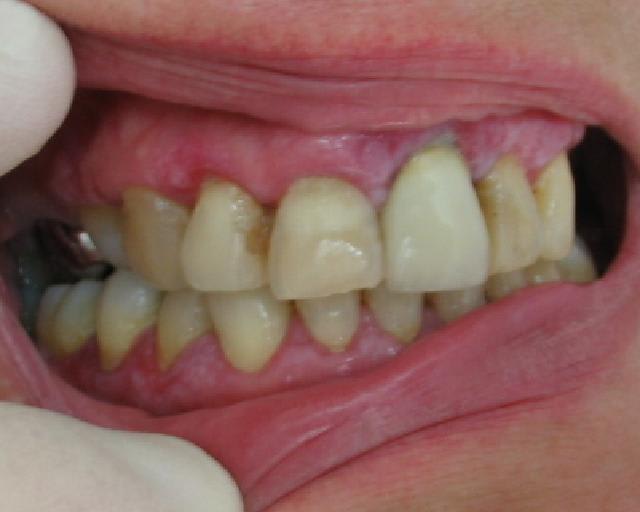

patiente de 50ans, consulte pour douleur et saignement gingival.

problème hépatique sous traitement( diagnostic précis non obtenu),pas d'autre medicament pris.

premier traitment il y a un mois : 10j jour de metronidazole à 1.5g/j puis traitement eau oxygéné+ bicarbonate + prexidine 1mois.

moins de douleur mais toujours les ulcérations.

la muqueuse est souple au touché ,inflammée, des poches sont presentes mais modérées 3-5mm.

les photos sont moyennes mais à mon avis il y a un lichen plan generalisé arrete l'eau oxygénée ( aggrave le lichen plan) et prend contact avec le gastro entero car il y a un rapport entre ses pbs hepatiques et le lichen plan peut être

fais une biopsie qui te permettra très vite de poser le diag

photo d'un lichen plan erosif pour comparer avec ce que tu as en bouche et la discussion eugenolienne